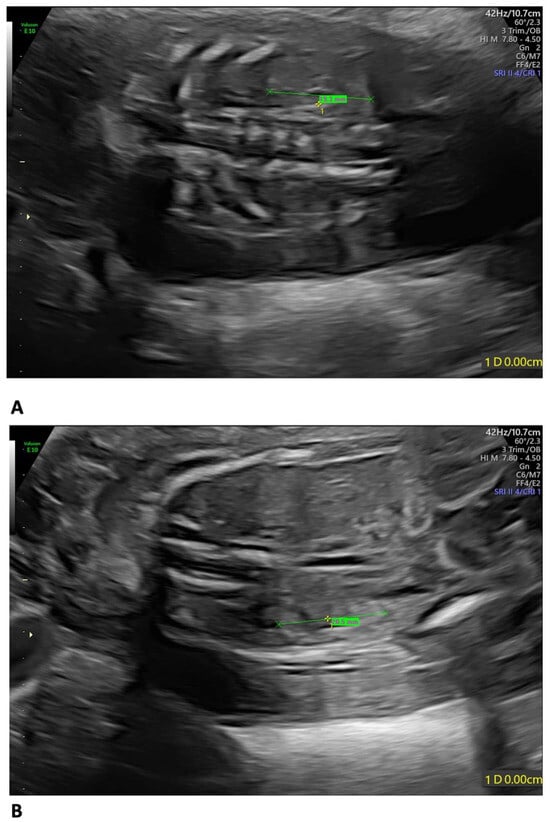

Background: The purpose of this study was to examine the relationship between qualitative characteristics and quantitative parameters from contrast-enhanced ultrasound (CEUS) and microvessel density (MVD) in hepatoblastoma (HB), as well as to investi...